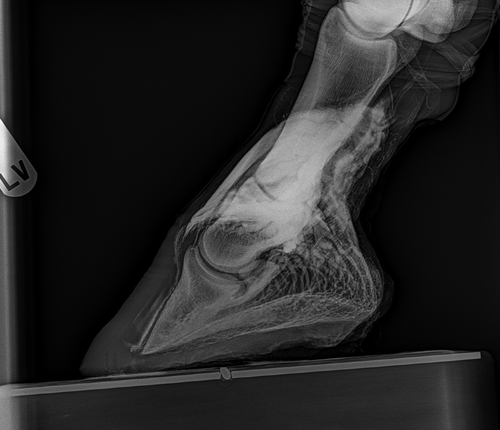

In der Pferdemedizin sind Huferkrankungen, deren Diagnostik und Therapie ein essentieller Baustein, denn weiter gilt, ohne Huf kein Pferd.

Angefangen bei Stellungskorrekturen bei Fehlstellungen von Fohlen, über Hufrehe, orthopädische Beschläge zur Entlastung, Beschlagskorrekturen, präventive Maßnahmen um Überbelastung zu verhindern, bis hin zur Versorgung von Verletzungen und chirurgische Eingriffe im Bereich des Hufes.

Alle diese Herausforderungen erfordern eine präzise Diagnostik und ein erfahrenes Team aus Tierärzten und Hufschmieden um die ideale Lösung für das individuelle Pferd zu finden.

Hufrehe ist mittlerweile der zweithäufigste Grund für die Euthanasie eines Pferdes. Durch eine gute Diagnostik und eine schnell eingeleitete Therapie können aber viele Pferde gerettet werden.